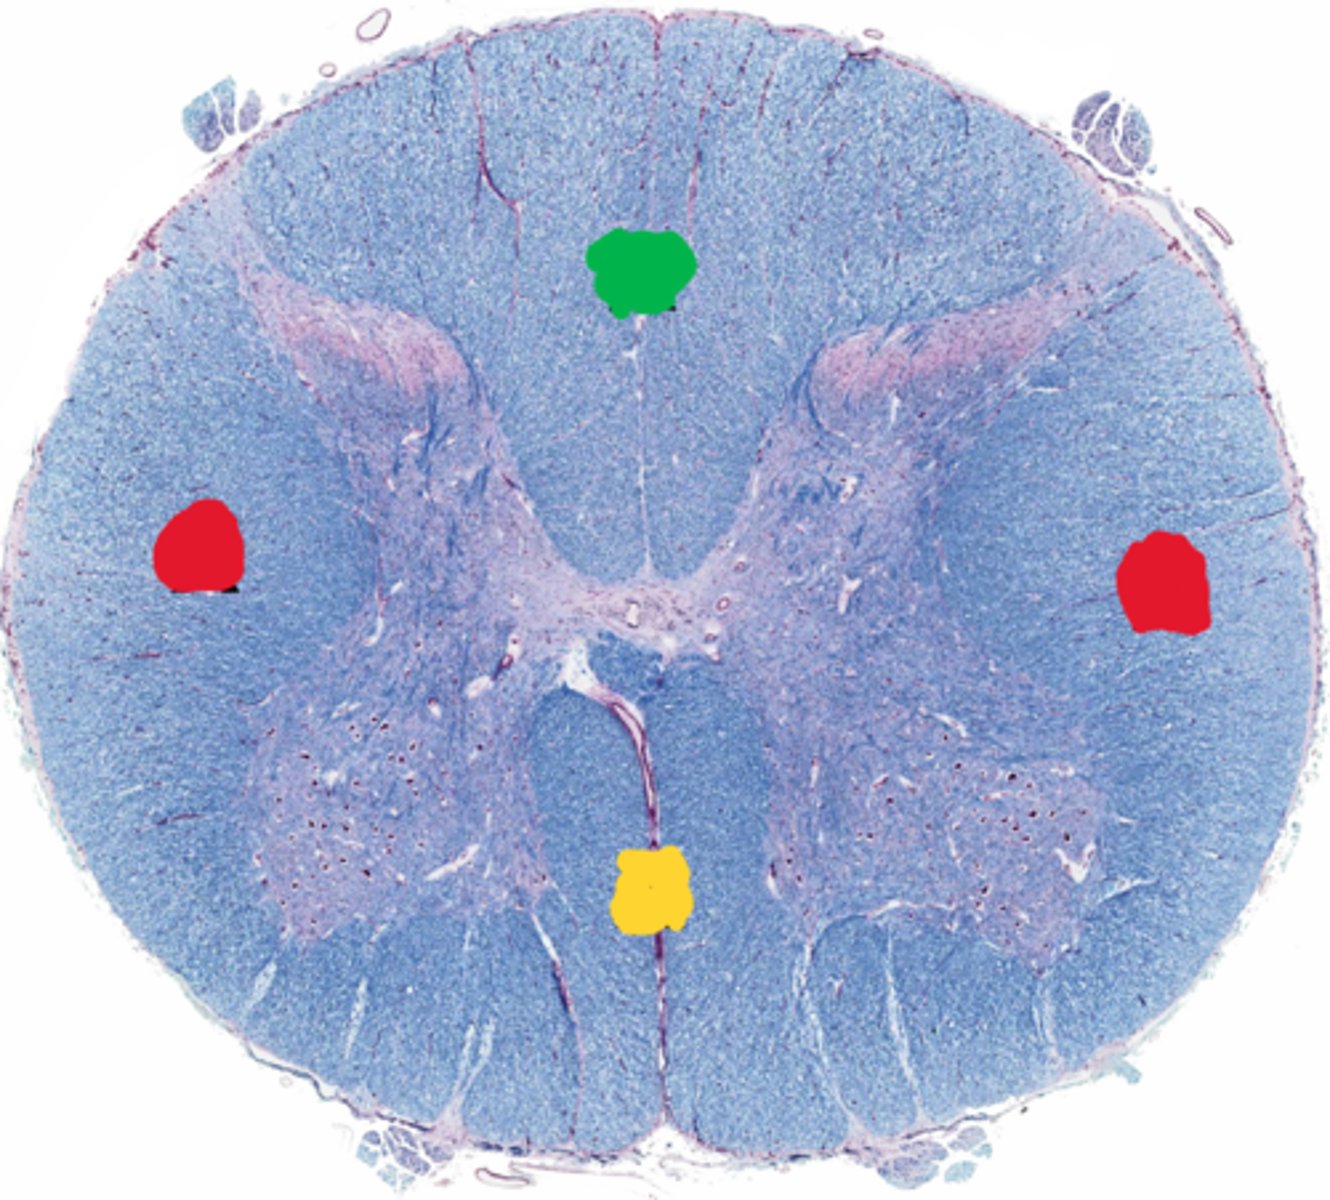

Posterior funiculus

Green

Anterior funiculus

Yellow

Lateral funiculus

Red

Posterior median sulcus

green

Anterior median fissure

red